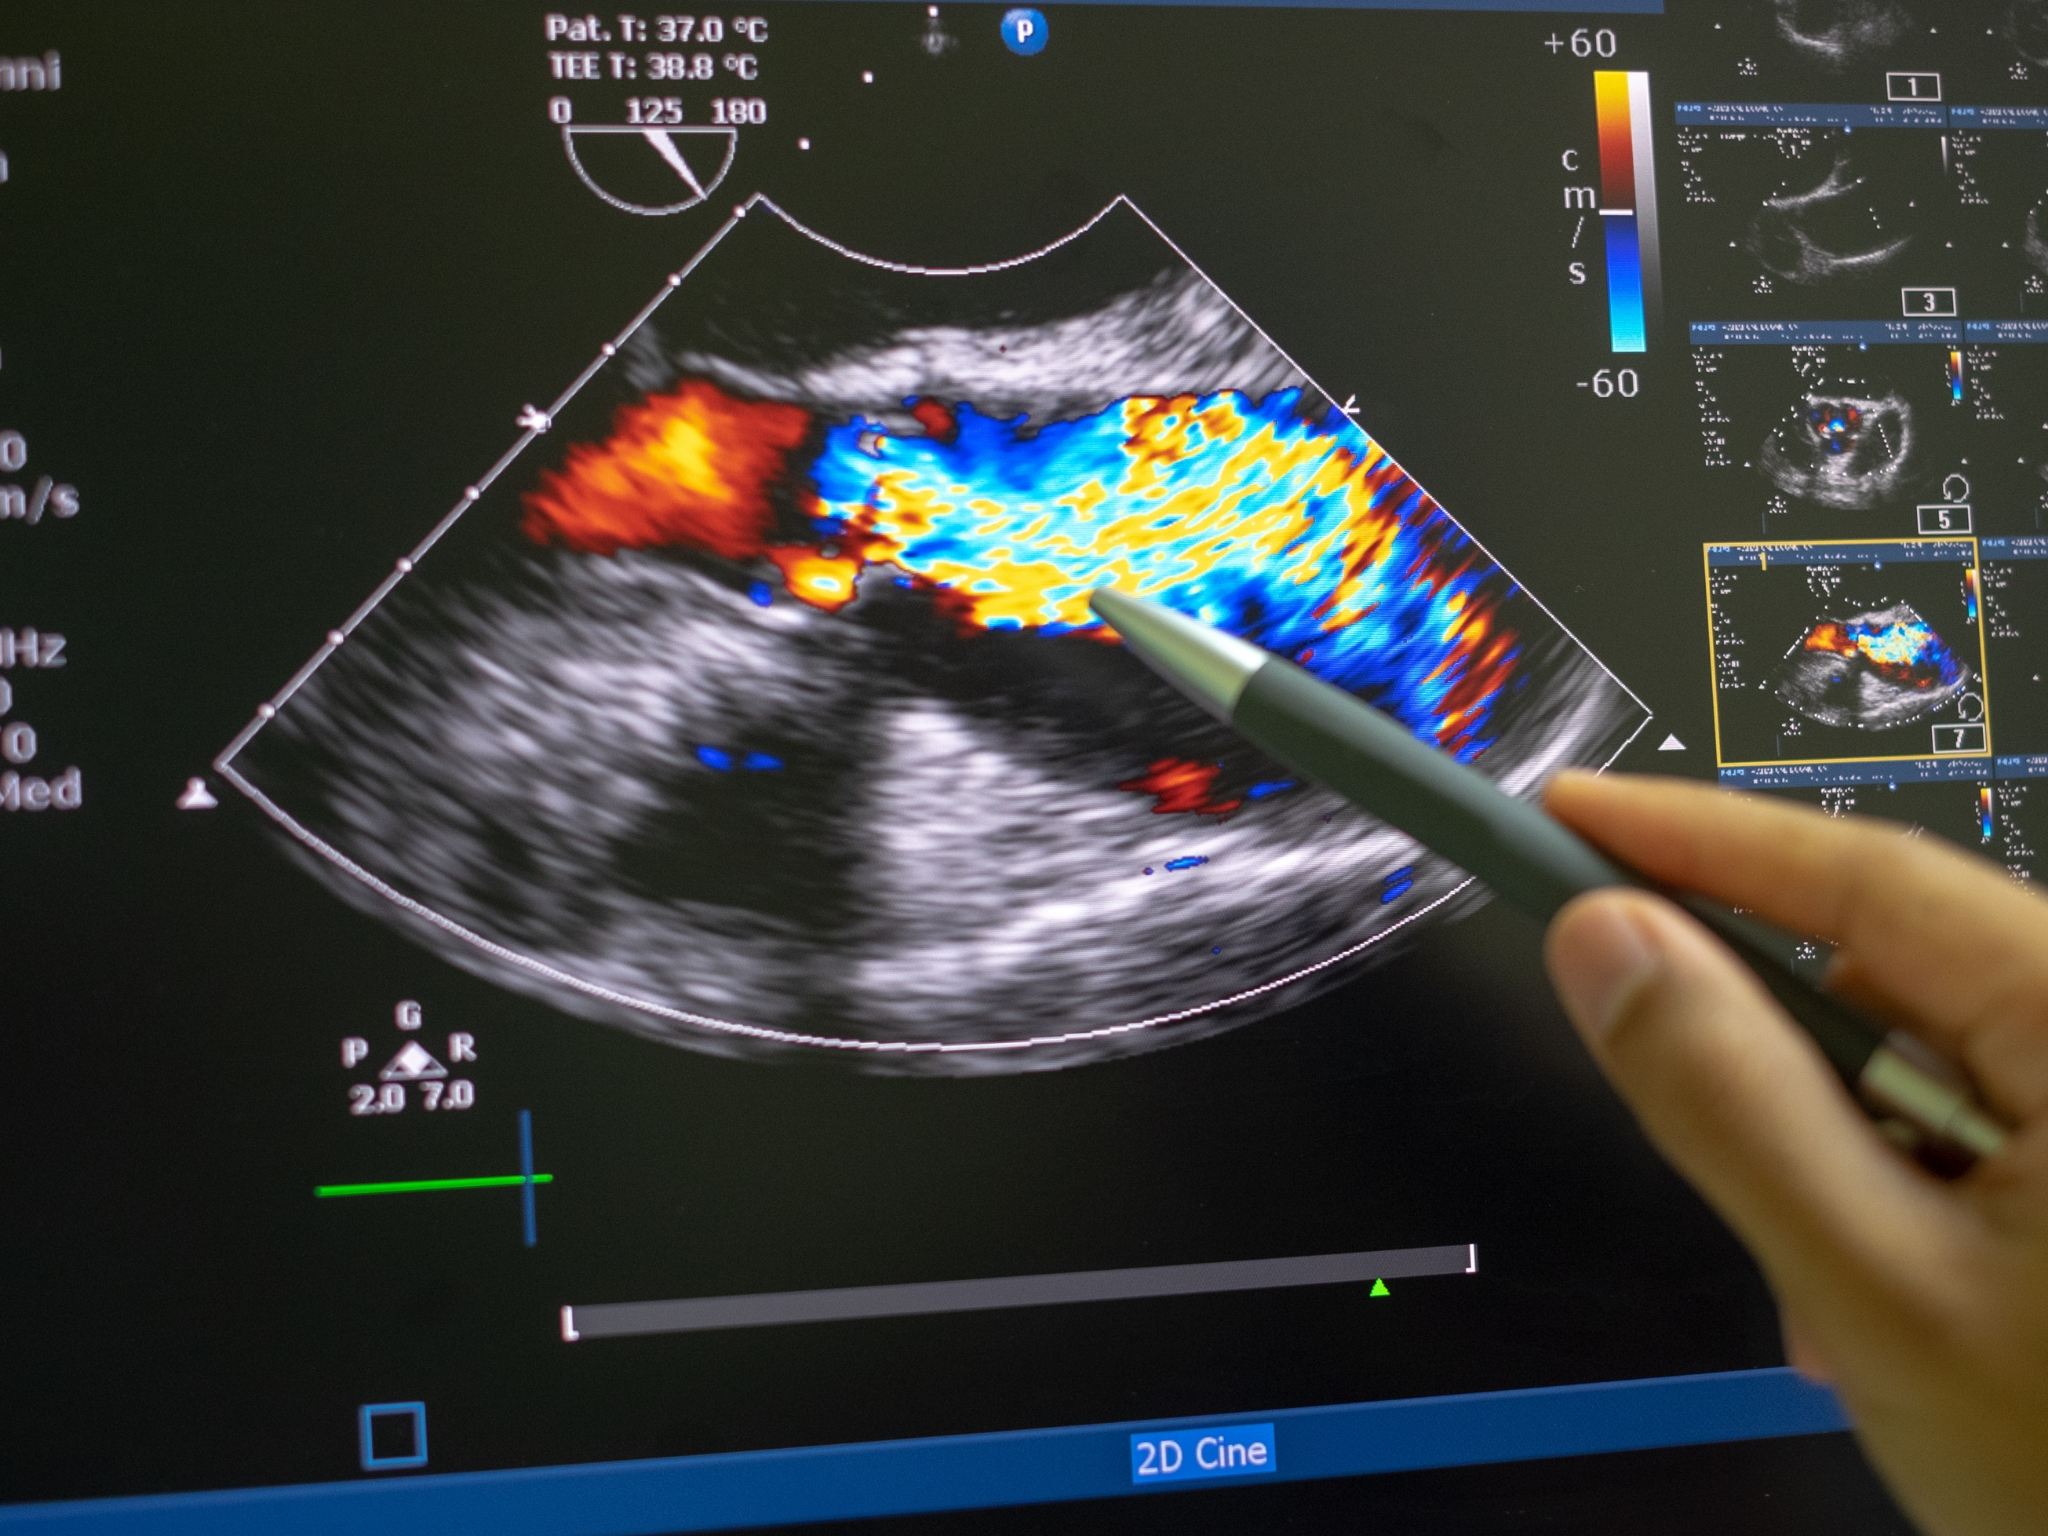

- Ecocardiografia adulti (Ecocuore)

- Ecocardiografia pediatriche (Ecocuore)

- Ecocolordoppler arterioso-venoso